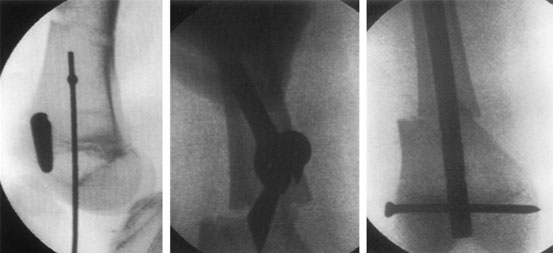

These are x-ray pictures taken during surgery. The left one shows the path of entry of the guide wire as seen from the side.

The picture in the center shows how the bone is translated(shifted on the long axis) at the osteotomy site. This is done in accordance with osteotomy rule 2(i.e when the osteotomy is away from the CORA-center of rotation axis.)

The picture on the right shows the final picture after the insertion of the intra-medullary nail in the corrected position with locking bolt holding the nail to the bone.